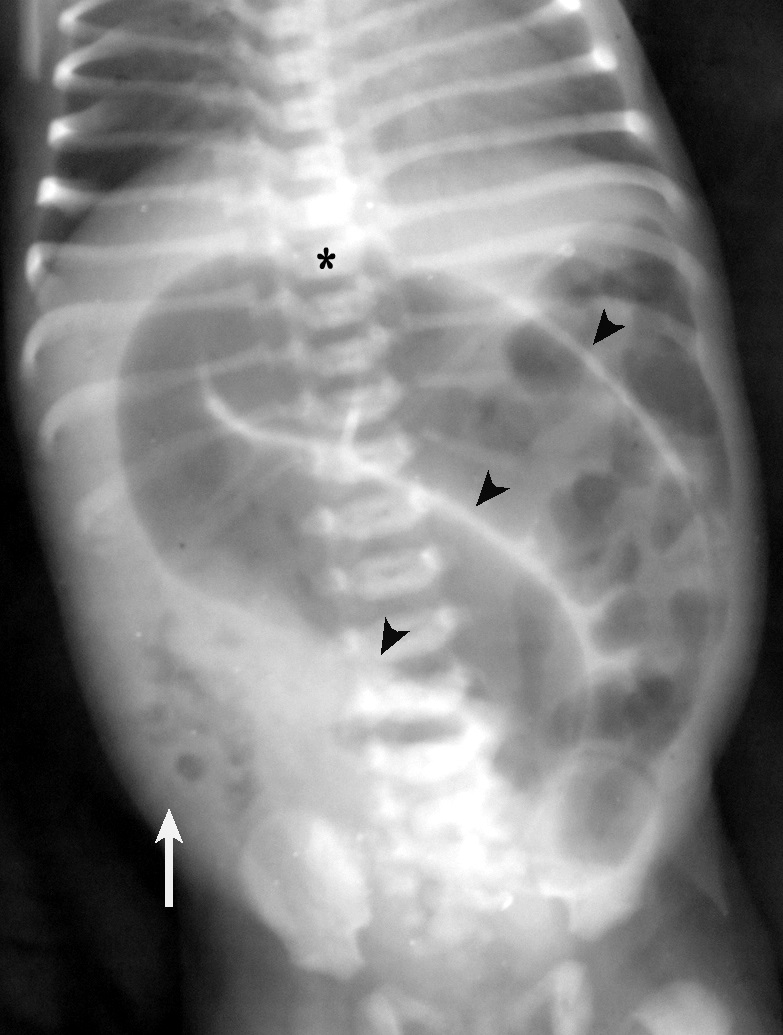

A newborn female was admitted 12 hours after birth with neonatal intestinal obstruction. Physical examination revealed a patent anus. Her abdomen was tensely distended. The plain radiograph showed the typical Friemann-Dahl sign. The apex of the distended bowel loop was at the level of the 8th thoracic vertebral body. Walls of the folded bowel were seen as three opaque lines converging towards the left iliac fossa (Fig. 1). All these features were suggestive of sigmoid volvulus. Scrutiny of the film also showed fine bubbles of gas in the right lower quadrant (Neuhauser’s sign). A contrast enema was not done because of the clinical suspicion of bowel ischemia.

Plain radiograph showing Friemann-Dahl’s sign with converging lines towards the left iliac fossa (black arrowheads) and air bubbles (Neuhauser’s sign) in the right lower quadrant (white arrow). A black asterisk marks the D8 vertebra.